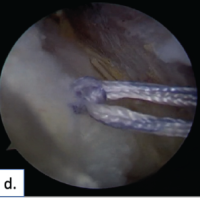

Among the study patients, external fixation was achieved either with the Ilizarov ring fixator or the LRS. A representative case from the Ilizarov group is illustrated in Fig. 1, while two patients treated with the LRS fixator is shown in Fig. 2 and 3.

Figure 3: 33-year-old male patient of compound Grade 3B diaphyseal fracture of the tibia and fibula presenting after 4 weeks of injury. (a) Radiograph at presentation (b) radiograph after 1 month of limb reconstruction system (LRS) application and corticotomy. Patient was lost to follow-up resulting in union at the corticotomy site (c) intraoperative images of repeat corticotomy at the proximal tibia and osteotomy of the mid diaphysis of tibia. (d) 3 month follow-up radiograph showing regenerate formation and completion of distraction. (e) 9 months follow-up radiograph showing complete consolidation of the regenerate and union at the compression site (f) final radiograph after LRS removal.